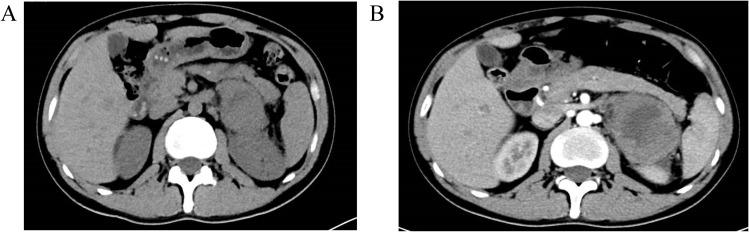

Pulmonary mucinous epithelioid carcinoma (PMEC) is a rare malignancy that typically progresses slowly and has a favorable prognosis. In contrast, adrenal sarcomatoid carcinoma (ASC) is an aggressive and uncommon cancer with poor outcomes. The coexistence of low-grade PMEC and metastatic ASC is exceedingly rare and presents unique clinical challenges, with limited treatment options and poor prognosis. This case report highlights the diagnosis and management of a patient with long-term, slow-progressing low-grade PMEC and rapidly progressing metastatic ASC.

CASE PRESENTATION

A 44-year-old male with a 20-year history of intermittent respiratory symptoms developed abdominal pain and imaging findings indicative of adrenal metastasis and multiple bone metastases. Initial diagnosis through CT and PET-CT scans raised suspicion for pulmonary tumors, and subsequent biopsies confirmed low-grade PMEC in the lungs. In 2023, further diagnostic work revealed a sarcomatoid carcinoma (SC) in the left adrenal gland. Molecular testing revealed BRAF p.V600E mutations across lung, adrenal, and plasma samples, providing critical insight into the nature of the metastatic spread. Despite treatment with molecular therapy (dabrafenib + trametinib) and radiotherapy, the patient's conditioan deteriorated rapidly, and he passed away in September 2023.

肺黏液性上皮样癌(PMEC)是一种罕见的恶性肿瘤,通常进展缓慢,预后良好。相比之下,肾上腺肉瘤样癌(ASC)是一种侵袭性强且罕见的癌症,预后较差。低级别PMEC与转移性ASC共存极为罕见,带来了独特的临床挑战,治疗选择有限且预后不良。本病例报告重点介绍了一名患有长期、进展缓慢的低级别PMEC和快速进展的转移性ASC患者的诊断和治疗情况。

病例介绍

一名44岁男性,有20年间歇性呼吸道症状病史,出现腹痛,影像学检查发现肾上腺转移和多处骨转移。通过CT和PET-CT扫描初步诊断怀疑肺部有肿瘤,随后活检证实肺部为低级别PMEC。2023年,进一步诊断发现左肾上腺有肉瘤样癌(SC)。分子检测显示肺、肾上腺和血浆样本中均存在BRAF p.V600E突变,为转移扩散的性质提供了关键见解。尽管接受了分子治疗(达拉非尼+曲美替尼)和放疗,患者病情仍迅速恶化,于2023年9月去世。